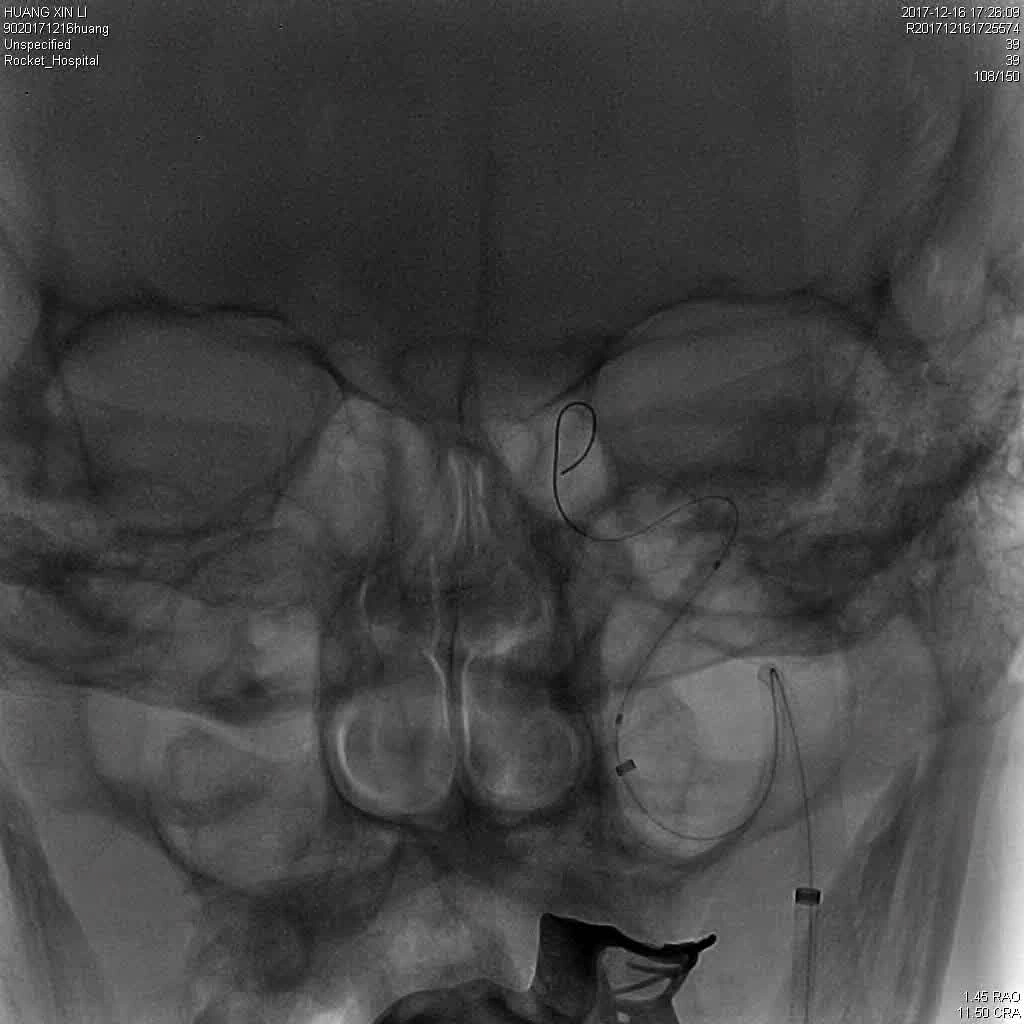

DSA显示ICAO

微导管造影证实MCAO

手术过程

中间导管配合在长鞘和小球囊的配合下穿过迂曲夹层的颈内动脉。

微导管微导丝越过MCA闭塞段,置入取栓支架支架。

微导管微导丝穿过夹层段,4.0×20mm球囊再次反复贴附夹层段,促进内膜贴壁。

造影观察,管腔狭窄较前好转,血流状态稳定,结束手术。